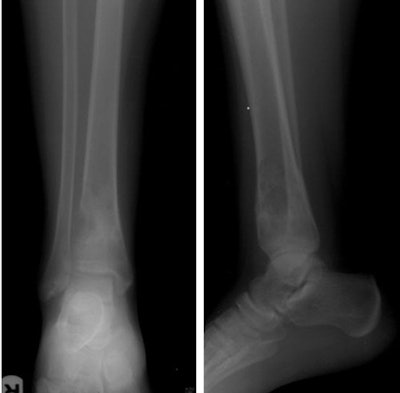

A 15-year-old boy presented with a metaphyseal lucent lesion with well-defined borders that remained quiescent for two years. The patient recently complained of persistent pain and progressive appearance of right ankle swelling. X-ray showed complete changes of the lesion's behavior into a punched-out defect of the distal tibial metadiaphyseal lesion with violated cortex and indeterminate zone of transition, no periosteal reaction or matrix formation were identified. The differential included ruptured chronic bone abscess, Langerhans cell histiocytosis (LCH), and marrow neoplasia. CT-guided biopsy was planned through the large exophytic soft-tissue component seen on CT. This allowed harvesting multiple cores from the main lesion within the bone. The biopsy returned with the result of fibroblastic osteosarcoma. Above, x-ray distal both leg bones and ankle in anteroposterior (left image) and lateral (right image) projections showing distal tibial metadiaphyseal cortical and eccentric lesion with cortical defect and indeterminate medial margin. Neither periosteal reaction nor matrix formations are recognized. Below, axial CT scans of the distal tibial lesion in soft-tissue window setting prior to start of the CT-guided procedure (left image) and bone window setting during the procedure (image at right). All images courtesy of Dr. Mohamed Ragab Nouh.